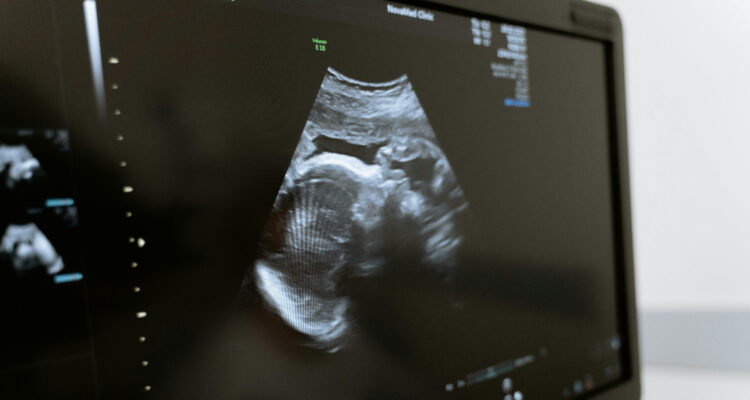

Un feto fue tratado dentro del útero por atrofia muscular espinal, un trastorno genético que puede llegar a ser mortal en recién nacidos. Este hito permitirá considerar tratamientos prenatales para esta enfermedad rara que afecta 1 de cada 10.000 nacimientos.

Por primera vez, un feto fue tratado dentro del útero por un complejo trastorno genético que, una vez que naciera, sería mortal para el bebé. Hoy tiene dos años y está sano, según reporta el caso médico.

El feto en gestación fue diagnosticado con atrofia muscular espinal, una enfermedad genética que afecta a las neuronas motoras que controlan el movimiento y además provoca debilitamiento progresivo en los músculos.